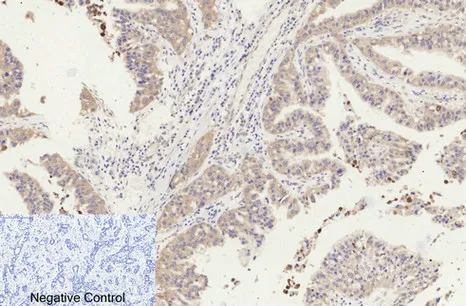

Cleaved-Caspase-8 (D384) Rabbit Polyclonal Antibody

Cat: APRab08968